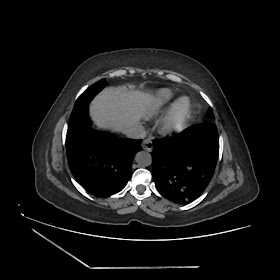

A 70 years old woman with Obstractive jaundice & palpable GB

Latest Radiological images: